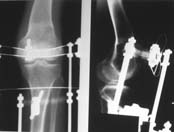

К сожалению, подобное осложнение "нет-нет да и возникает" при удлинении, коррекции деформации голени. В англоязычной литературе оно описано как "patella baja". Один из вариантов лечения - проксимальное перемещение надколенника приемами чрескостного остеосинтеза.